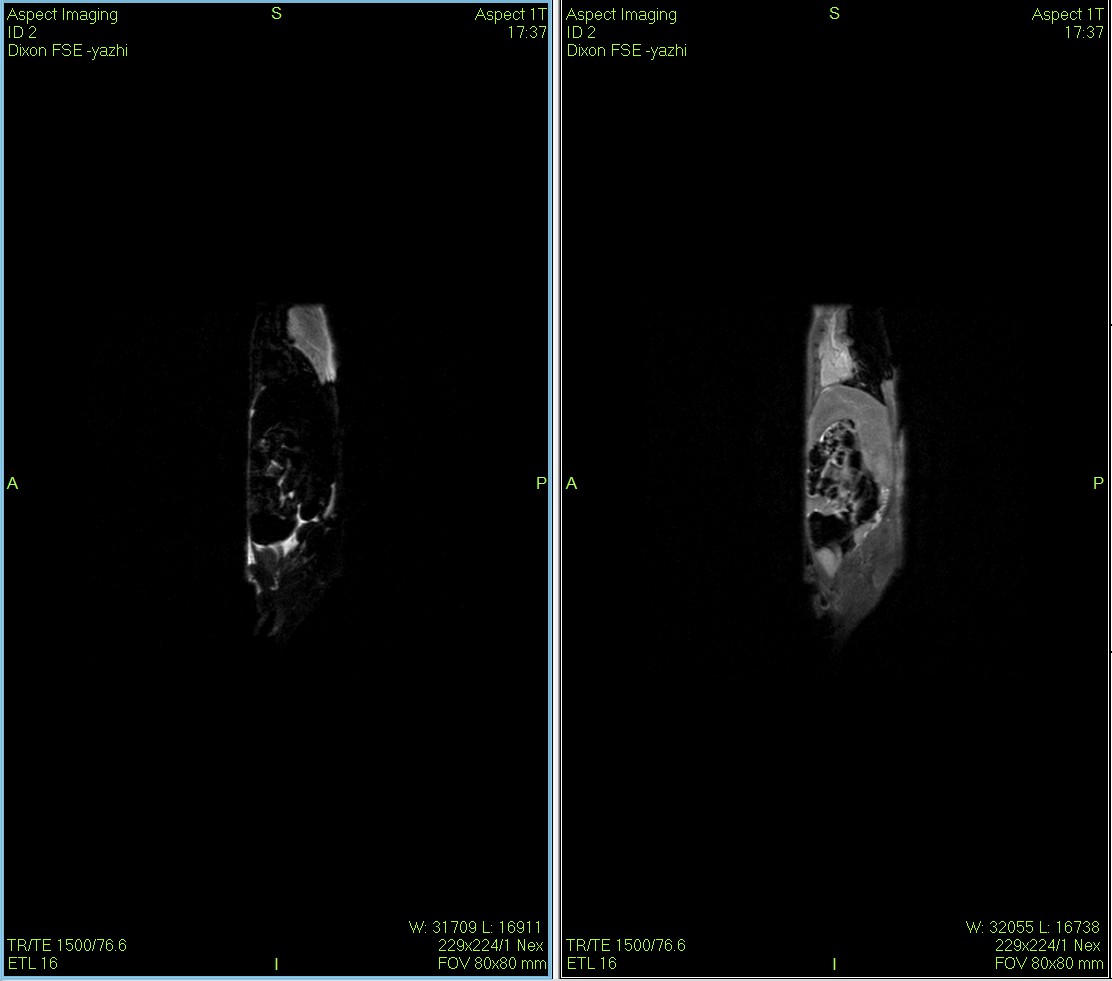

The Dixon fat suppression technique, originally proposed by Dixon, is based on the chemical shift difference between water and fat protons.By using different echo times, it acquires two sets of signals: one where water and fat protons are in phase, and another where they are opposed in phase.This enables the effective separation of water and fat signals in magnetic resonance imaging.